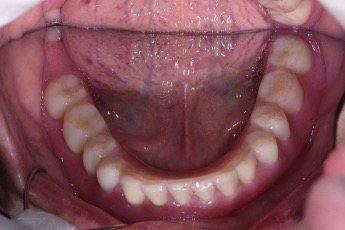

下顎植牙兩顆-林錫奎醫師

下顎植牙兩顆

安裝後